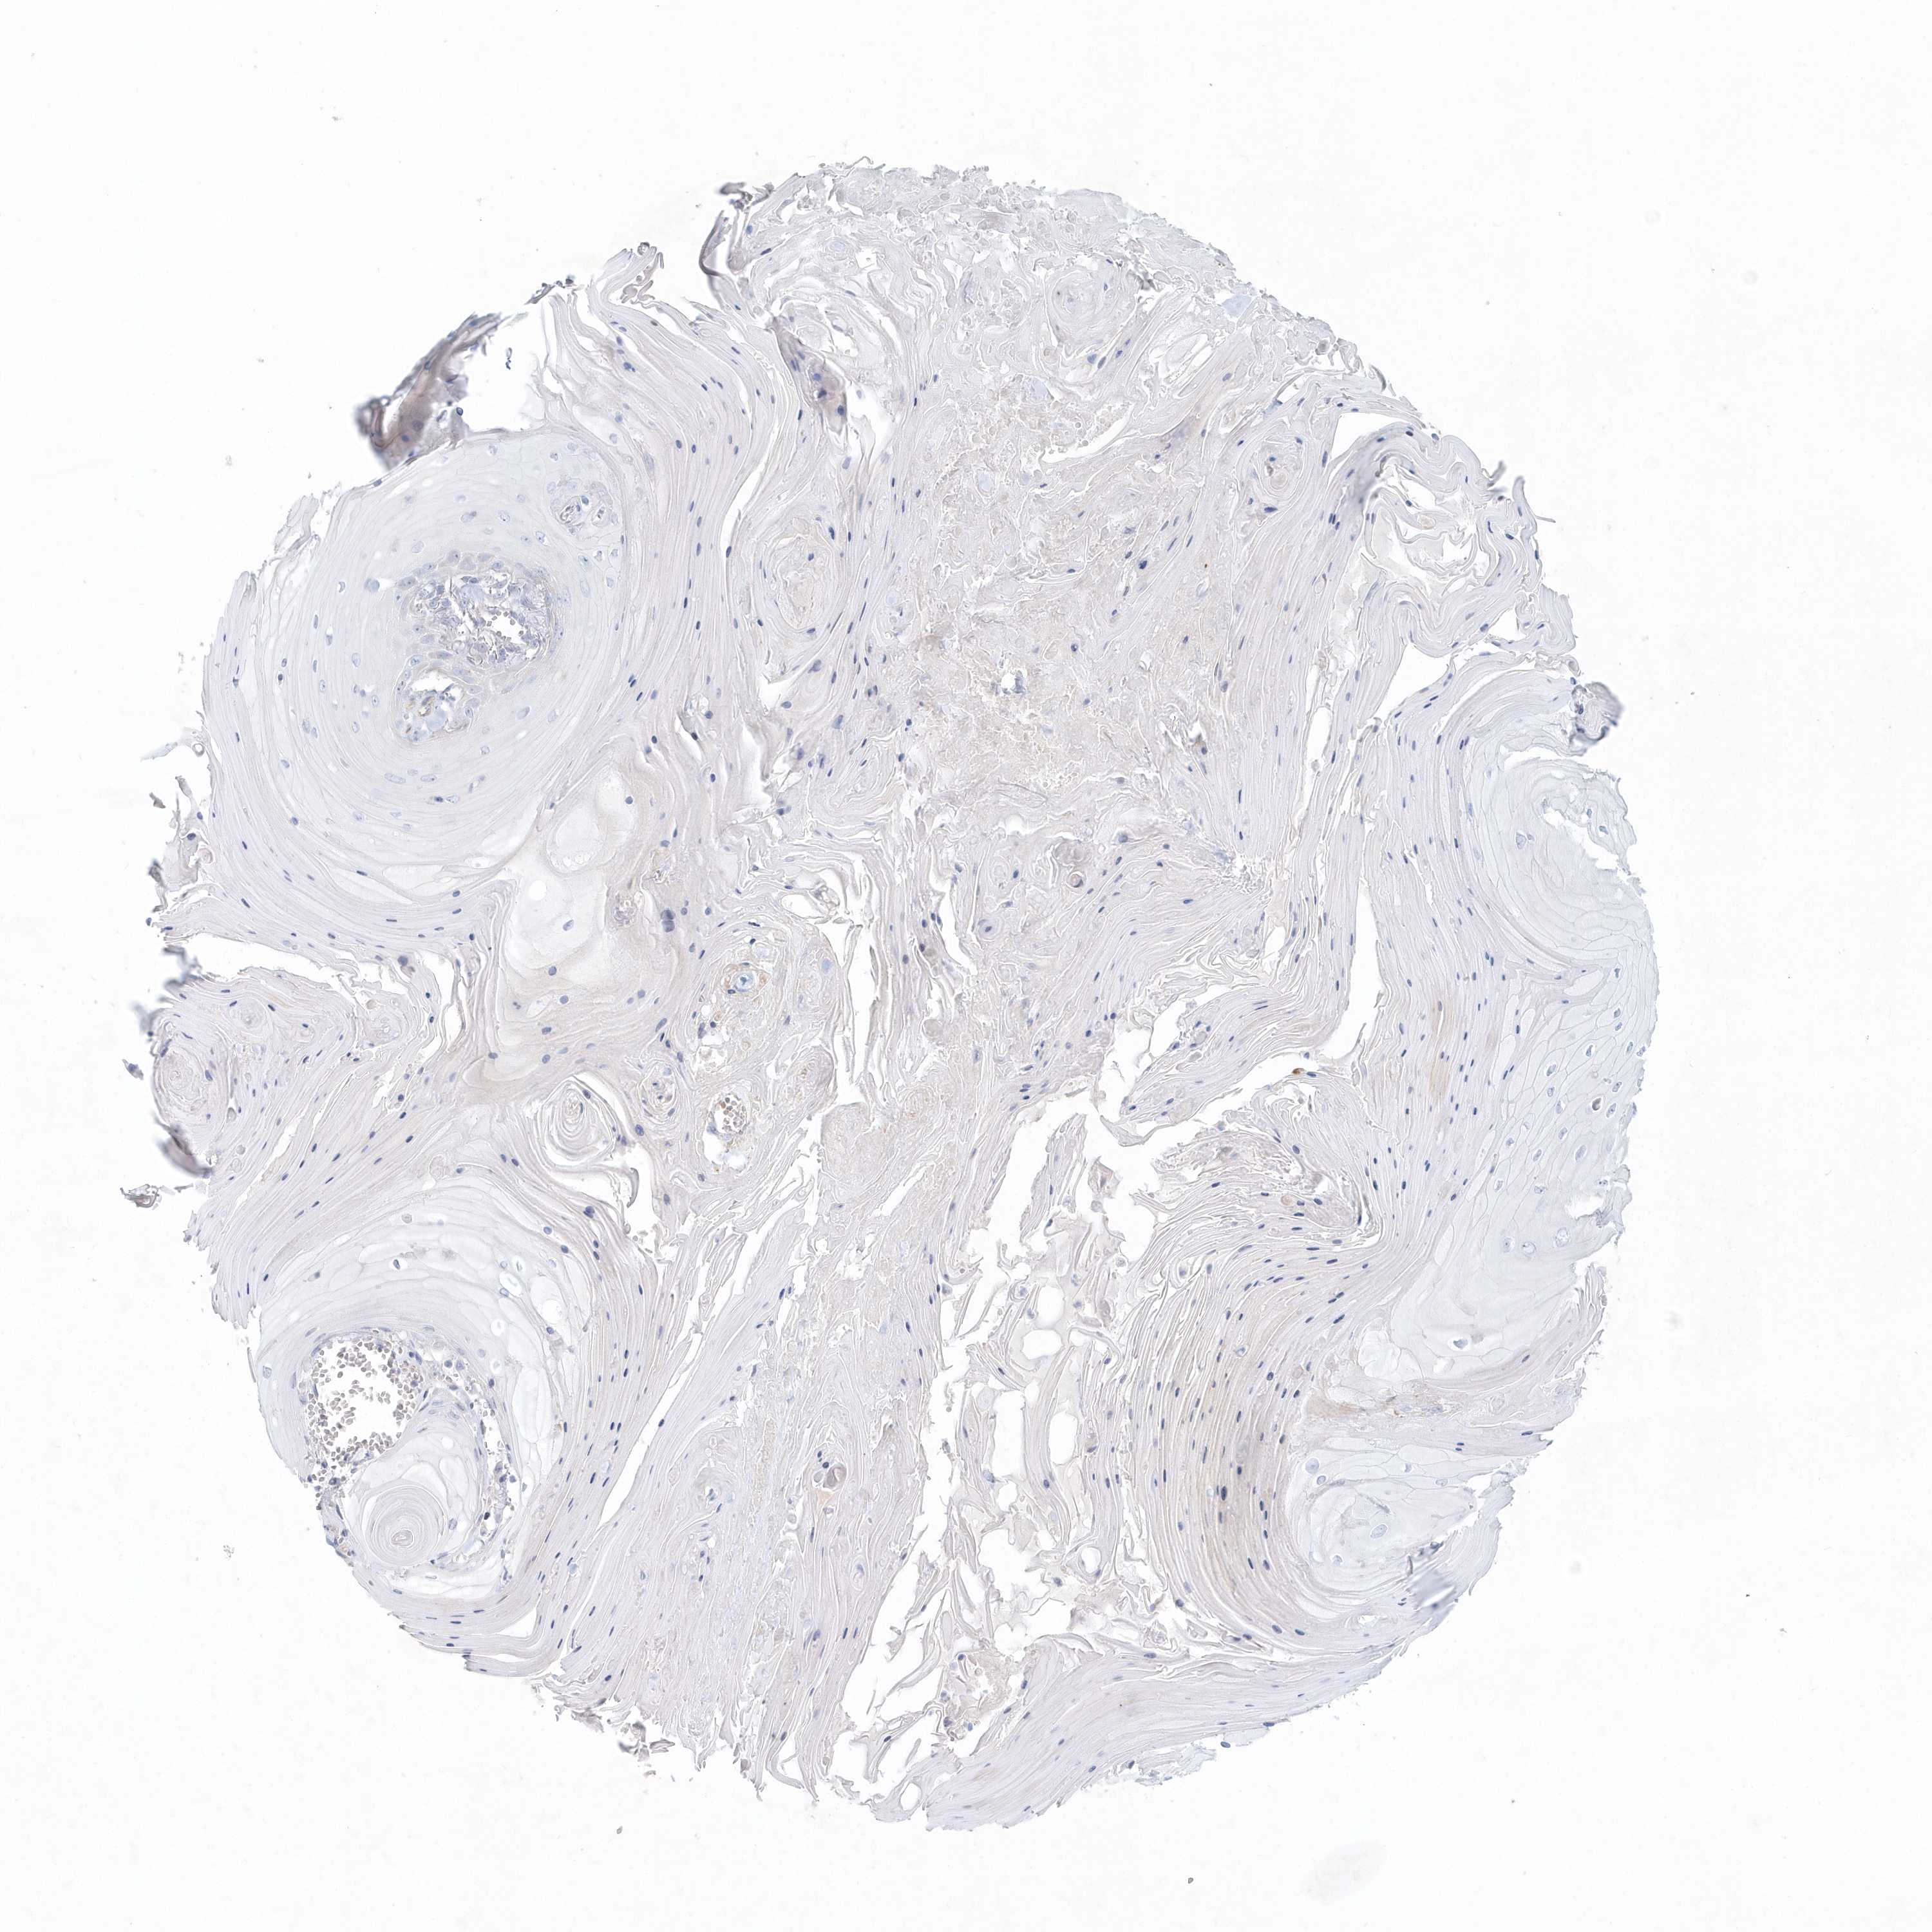

SKIN CANCER - Protein expressioni

A mouse-over function shows sample information and annotation data. Click on an image to view it in a full screen mode. Samples can be filtered based on level of antibody staining by selecting one or several of the following categories: high, medium, low and not detected. The assay and annotation is described here.

Each image is clickable and will lead to virtual microscopy that enables deeper exploration of all samples and also displays staining intensity scores, fraction scores and subcellular localization as well as patient and tissue information for each sample.

Antibody HPA036805

Basal cell carcinoma